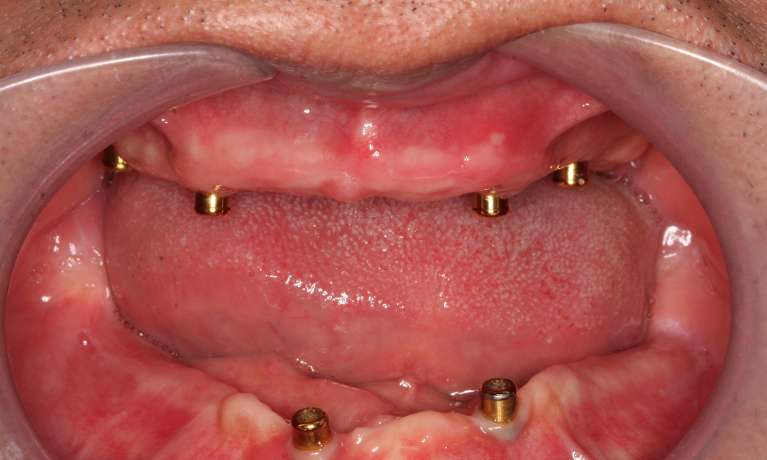

Implant All-on-4® dentures—All-on-4 dentures are implant-supported dentures that are permanently anchored in the mouth. Their streamlined design makes the denture wearing process easier on your diet and speech. Instead of covering the roof of your mouth, implant dentures cover only the jawline.